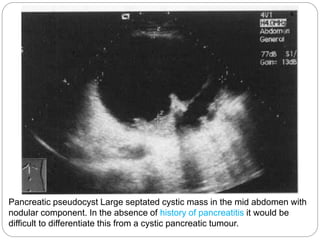

Pancreatic pseudocyst Large septated cystic mass in the mid abdomen with

nodular component. In the absence of history of pancreatitis it would be

difficult to differentiate this from a cystic pancreatic tumour.

Pancreatic pseudocyst Largeseptated cystic mass in the mid abdomen with nodular component. In the absence of history of pancreatitis it would be difficult to differentiate this from a cystic pancreatic tumour.